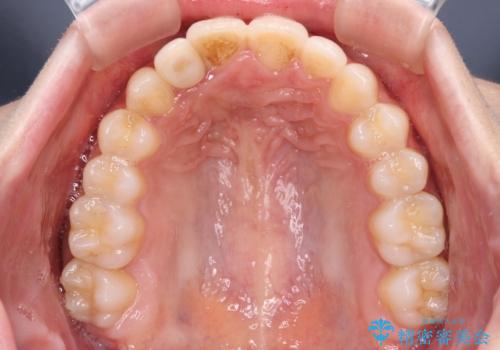

- 上下前歯のデコボコを気にして来院された患者様です。

前歯のセラミックが装着されている歯は、歯根が短くなっており、他院では抜けてしまうので矯正はできないと言われていたようです。

患者様と相談し、抜けてしまった場合にはインプラントあるいはブリッジによる補綴治療が必要となることを確認し、極力歯根に負担のかからないような仕上がりで治療を進めて行くこととしました。

デコボコを解消には、IPR(歯と歯の間を削る)をメインに歯列排列を設計し、インビザラインにて矯正治療を行うこととしました。

レントゲン写真上では、矯正治療前後で歯根長さに大きな違いはなく、抜歯を回避することができました。

上顎内側に転位している前から2番目の歯は移動が難しく、無理矢理歯根全体を動かそうと設計すると、歯肉退縮・歯髄壊死・歯根吸収といった危険性が増すため、無難なゴールにて治療を終えることとなりました。